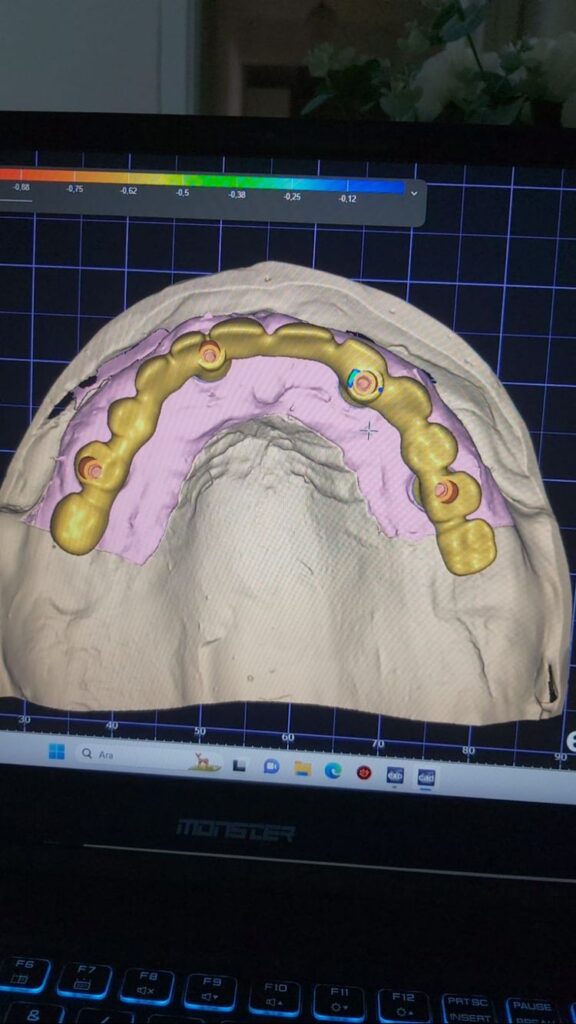

IMPLANT USTU ZIRKONYUM

IMPLANT USTU ZIRKONYUM ALT YAPI

MONOLITIK IMPLANT USTU ZIRKONYUM & ÜSTTEN ViDALI ZİRKONiUM

MULTILAYER IMPLANT ÜSTÜ ZIRKONYUM & ÜSTTEN VİDALI ZIRKONYUM

VIDALI IMPLANT USTU BAR (HER ABUTMENT BAŞI)